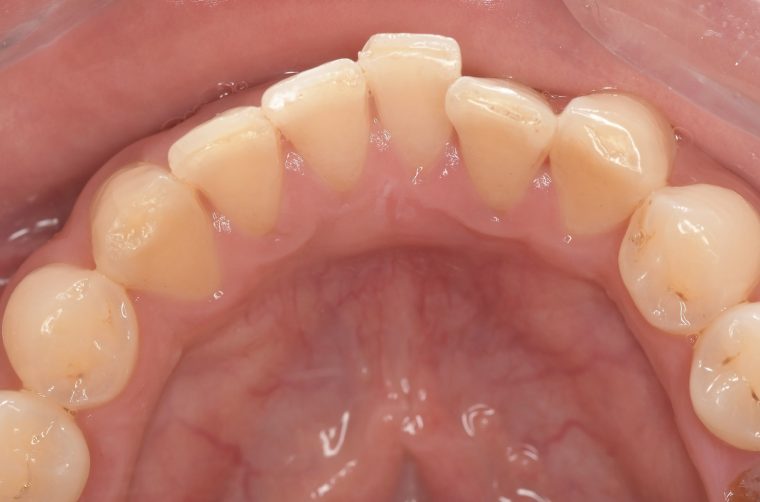

クリーニングの症例

現在の治療費と異なる場合がございます。最新の治療費は料金表をご確認ください。CASE 1

Before

After

基本情報

| 主訴 | 見た目をきれいにしたい |

| 治療期間 | 6ヶ月 |

| 治療費 | ジルコニアボンド(セラミックの被せもの)¥165,000×7(税込み) オフィスホワイトニング4回 ¥4,400×4(税込み) ホームホワイトニング¥11,000 |

| リスク・副作用 | かみ合わせがとても強い方の場合、稀に割れてしまうことがあります。 |

| 先生からの提案 | 上の前歯6本と右下の2番目の歯はセラミックの被せもので治療。 残りの下の前歯5本はプラスチックの材料で虫歯を治療し、 ホワイトニングをおこないました。白くなったご自身の歯の色に合わせてセラミックの 被せものを作成しています。 模型上で完成後をシュミレーションし、上の歯茎の位置をきれいに見えるように 揃えています。(外科処置はしていません) |